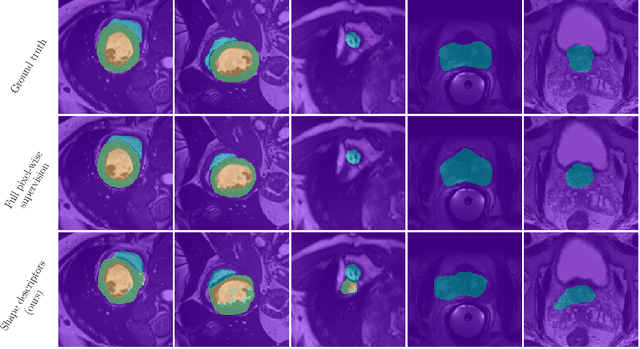

Abstract:Standard losses for training deep segmentation networks could be seen as individual classifications of pixels, instead of supervising the global shape of the predicted segmentations. While effective, they require exact knowledge of the label of each pixel in an image. This study investigates how effective global geometric shape descriptors could be, when used on their own as segmentation losses for training deep networks. Not only interesting theoretically, there exist deeper motivations to posing segmentation problems as a reconstruction of shape descriptors: Annotations to obtain approximations of low-order shape moments could be much less cumbersome than their full-mask counterparts, and anatomical priors could be readily encoded into invariant shape descriptions, which might alleviate the annotation burden. Also, and most importantly, we hypothesize that, given a task, certain shape descriptions might be invariant across image acquisition protocols/modalities and subject populations, which might open interesting research avenues for generalization in medical image segmentation. We introduce and formulate a few shape descriptors in the context of deep segmentation, and evaluate their potential as standalone losses on two different challenging tasks. Inspired by recent works in constrained optimization for deep networks, we propose a way to use those descriptors to supervise segmentation, without any pixel-level label. Very surprisingly, as little as 4 descriptors values per class can approach the performance of a segmentation mask with 65k individual discrete labels. We also found that shape descriptors can be a valid way to encode anatomical priors about the task, enabling to leverage expert knowledge without additional annotations. Our implementation is publicly available and can be easily extended to other tasks and descriptors: https://github.com/hkervadec/shape_descriptors